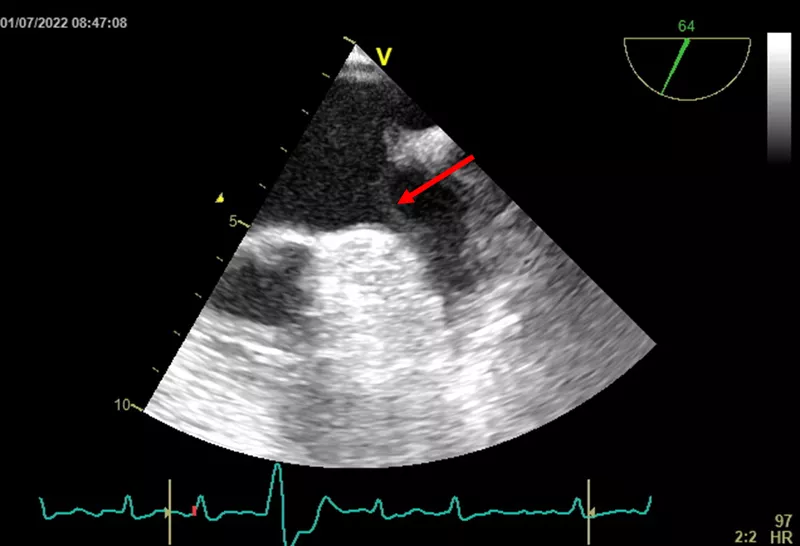

Pacientce jsme primárně podali metoprolol sukcinát v malé dávce 25 mg/den. Za hospitalizace bylo u pacientky provedeno echokardiografické vyšetření s překvapivým nálezem těžké systolické dysfunkce levé komory s EF 30 % při difúzní hypokinezi stěn. Příčinu této dysfunkce jsme viděli v kardiomyopatii indukované tachykardií (fibrilací síní). Z tohoto důvodu jsme chtěli tedy elektrickou kardioverzi provést co nejčasněji, a tak jsme u pacientky doplnili ještě transezofageální echokardiografické vyšetření (TEE) k vyloučení trombu ouška levé síně. V oušku však byl bohužel přítomen vláknitý trombus a od snahy o verzi arytmie bylo tedy za hospitalizace upuštěno. Pacientka byla s výhledem kontrolního TEE a elektrické kardioverze v dobrém neurologickém stavu propuštěna domů s následující terapií:

Image

Obr. 2. Transthorakální vyšetření s nálezem a vyznačením trombu